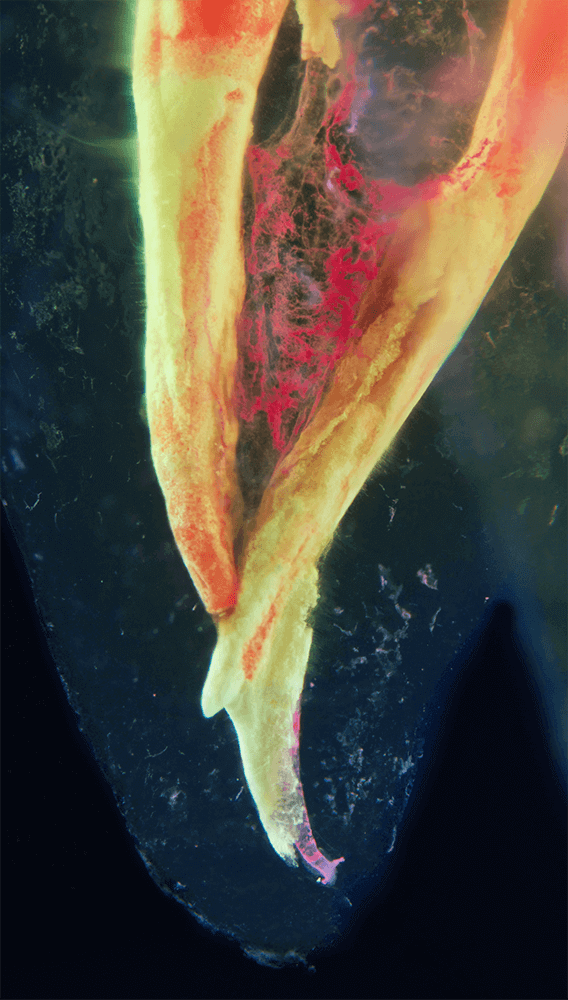

Das Verfahren, Zähne in durchsichtige Präparate zu überführen ist schon über 100 Jahre alt. Aber erst durch die Weiterentwicklung der alten Technik und die Kombination mit moderner Fotografie sowie der Entwicklung eines geeigneten Gefäßes zur Fotografie ist es meinem Vater Dr. Holm Reuver gelungen, einzigartige Bilder vom Inneren der Zähne aufzunehmen.

Die Bilder sind in verschiedenen Größen wählbar und auch als POPART-Variante erhältlich. Sie sind hervorragend geeignet für die Beratung von Patienten vor endodontischen Behandlungen, aber auch ein beliebter Eyecatcher im Wartezimmer. Außerdem haben die Bilder einen bedeutenden Stellenwert für die Erforschung der Pulpatopografie und für die Lehre im Bereich der Endodontie.

CLEARINGSERVICE bietet Ihnen die Möglichkeit, wurzelgefüllte Zähne mit der Technik des Transparentmachens untersuchen zu lassen. Das geht sehr einfach: Sie schicken uns den zu untersuchenden Zahn, dieser wird dann in ein transparentes Präparat überführt und mit hochwertiger Makrofotografie ausgewertet. Anschließend bekommen Sie die angefertigten Präparate zusammen mit der Fotodokumentation zugeschickt.